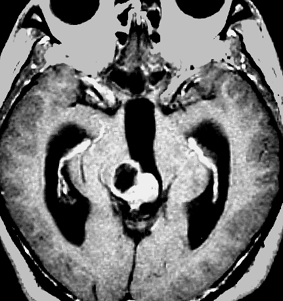

放射線化学療法後の画像です。腫瘍境界は不明瞭(左)で,腫瘍内出血(中央)して,左の視床に浸潤しています。かなりリスクは高いのですが,これを開頭手術で全摘出しました(右),この時点で完全寛解 CR です。この後にさらに化学療法と幹細胞移植(PBSCT,大量化学療法)が加えられました。